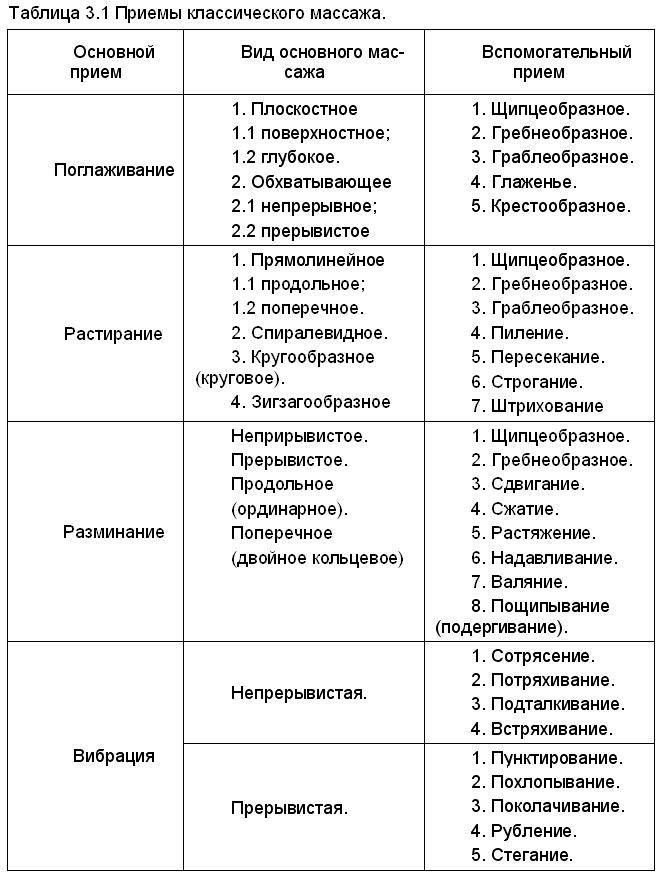

Диаграммы и схемы движения в суставах человека